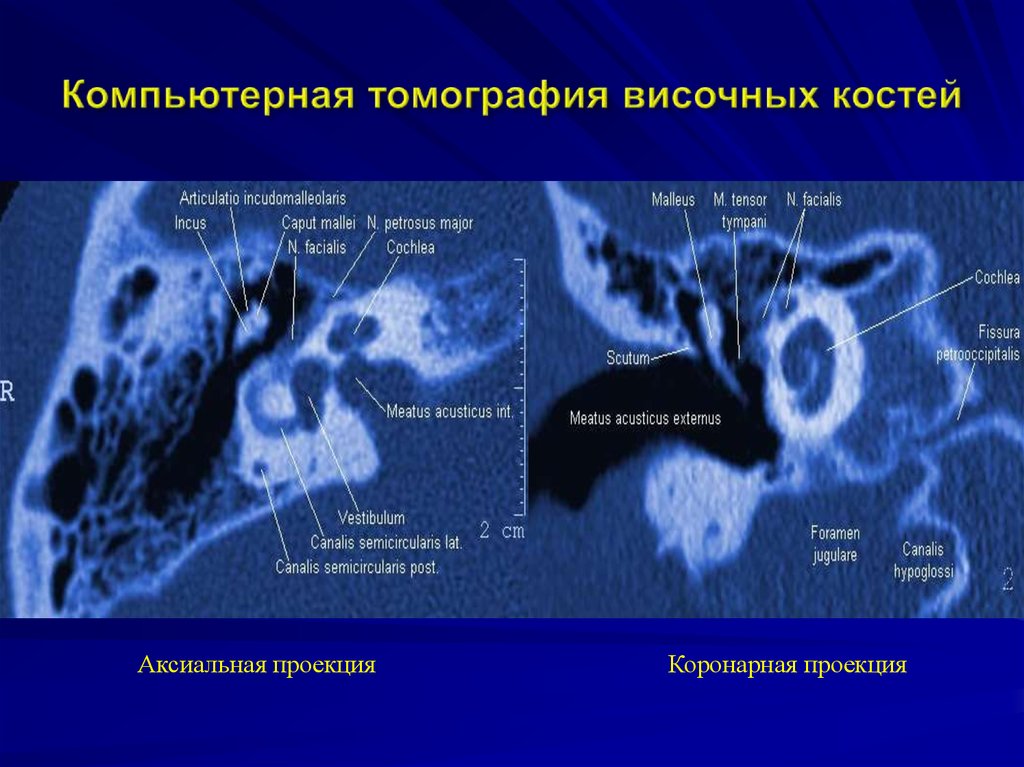

КТ анатомия сосцевидного отростка: особенности и показания